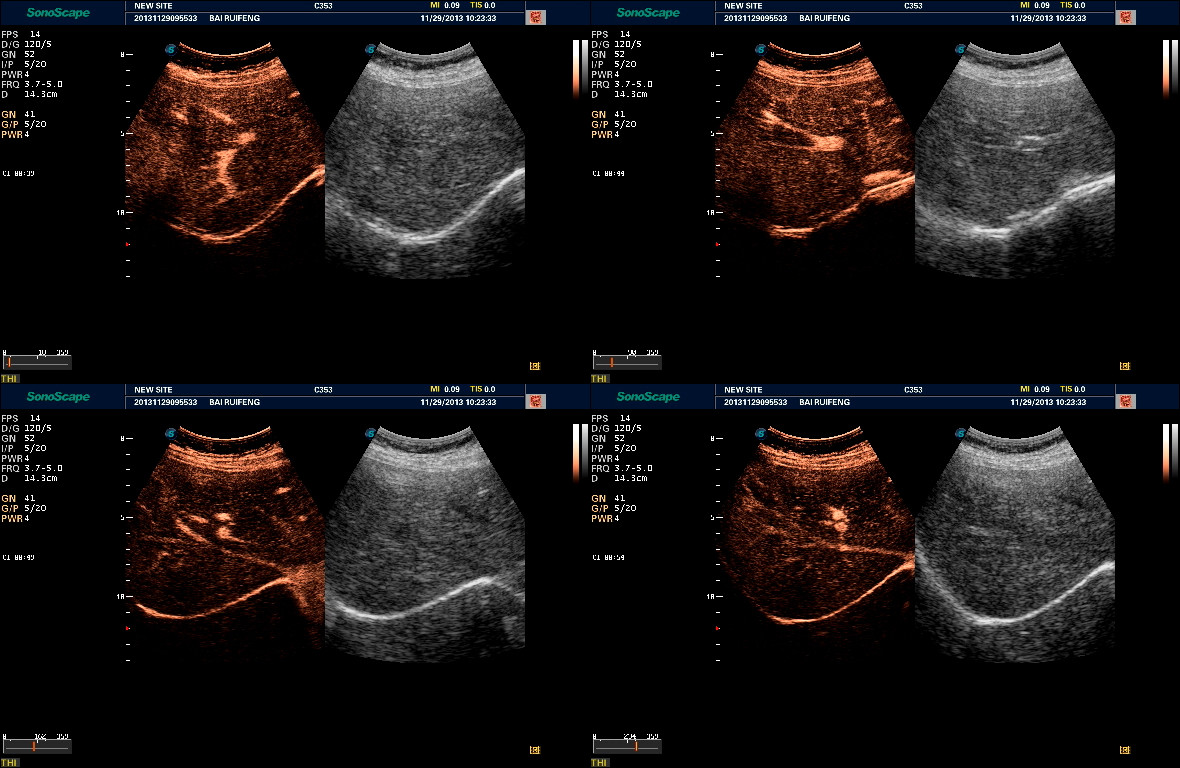

- Три технологии сосудистой визуализации – SRF, Bright Flow, Micro F для уверенной визуализации самых мелких сосудов

- Весь пакет допплеровских режимов, Strain Rate